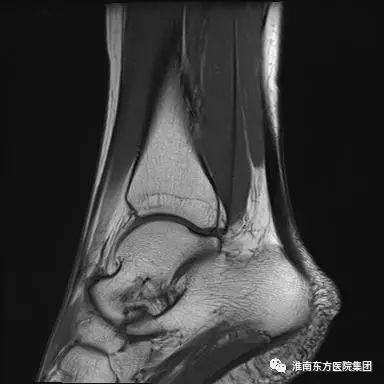

踝关节